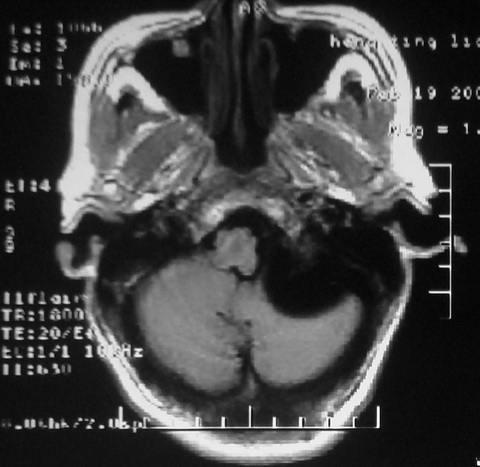

m,72,头疼,头晕两年,伴视力模糊三月,饮食呛咳两天。pe:颈部抵抗,左眼突出,左眼瞳孔约3mm,对光反射消失,双眼失明,伸舌困难,双肺呼吸音粗,心率110次/分,左上肢肌力i级,左下肢屈曲,肌张力高。现有08年2月19mri平扫及10年2月8日mri增强请会诊。ct病灶呈低密度伴散在点、片状等密度区,无明确钙化(无ct片资料可供上传)。[

脑外肿瘤,病灶呈匍匐蔓延,表皮样囊肿可能性大。

脑外肿瘤,病灶呈匍匐蔓延,表皮样囊肿可能性大。支持!